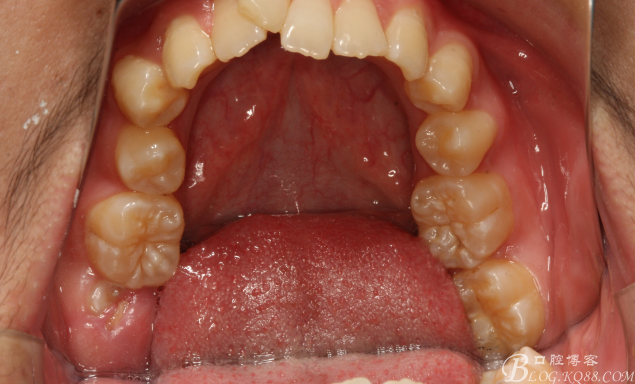

圖4.上腭部影像:腭側(cè)粘膜圓形隆起